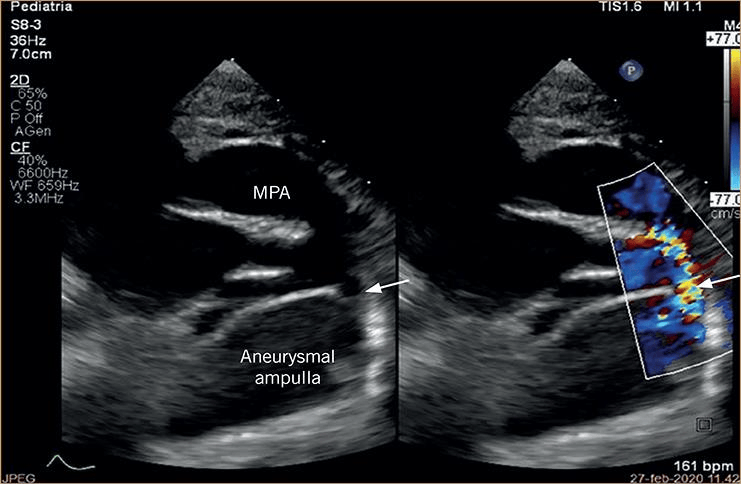

注意管状结构内皮上以及与肺动脉相通处周围的射流冲击损伤(箭头).